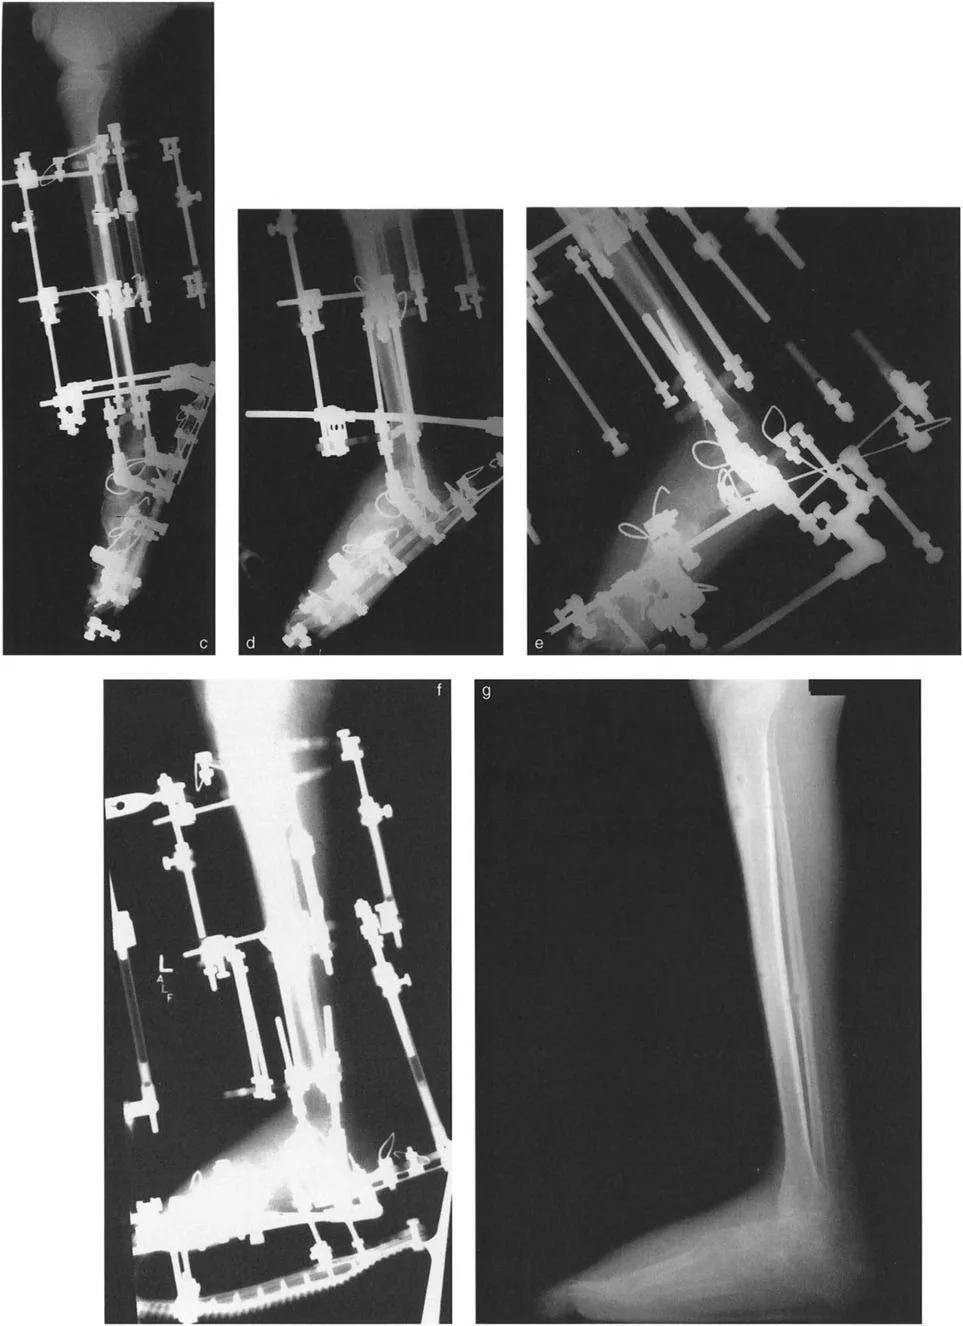

إزالة النتوءات العظمية وتعميق التلم الكاحلي

في حالات تقوس الكاحل الناتجة عن اصطدام عظمي (Bony Impingement) بسبب نتوءات عظمية في حافة الظنبوب الأمامية أو في التلم الظهري لعظم الكاحل، يقوم الأستاذ الدكتور محمد هطيف بإزالة هذه النتوءات وتعميق التلم الكاحلي للسماح لعظم الكاحل بالثني للأعلى بحرية.

* صورة توضح النتوءات العظمية التي تسبب اصطدامًا في الكاحل.

قطع العظم التصحيحي (Osteotomy)

عند وجود تشوهات عظمية مثل تقوس الظنبوب البعيد، قد يتطلب الأمر قطع العظم وإعادة توجيهه. على سبيل المثال، يمكن إجراء قطع عظم قبة ظهرية (Dorsiflexion focal dome osteotomy) في الظنبوب البعيد لتصحيح انحنائه.

تحرير الأنسجة الرخوة (Soft Tissue Release)

إذا لم يتم تحقيق التصحيح الكامل بعد تطويل وتر العرقوب، قد يكون هناك حاجة لتحرير إضافي للأنسجة الرخوة، بما في ذلك اللفافة العميقة الخلفية، وتحرير المحفظة، وتفكيك الالتصاقات داخل المفصل.

- تحرير النفق الرسغي (Tarsal Tunnel Release): يُوصى به وقائيًا في تصحيحات التقوس التي تزيد عن 10 درجات، لتقليل خطر إصابة العصب الظنبوبي الخلفي والأوعية الدم